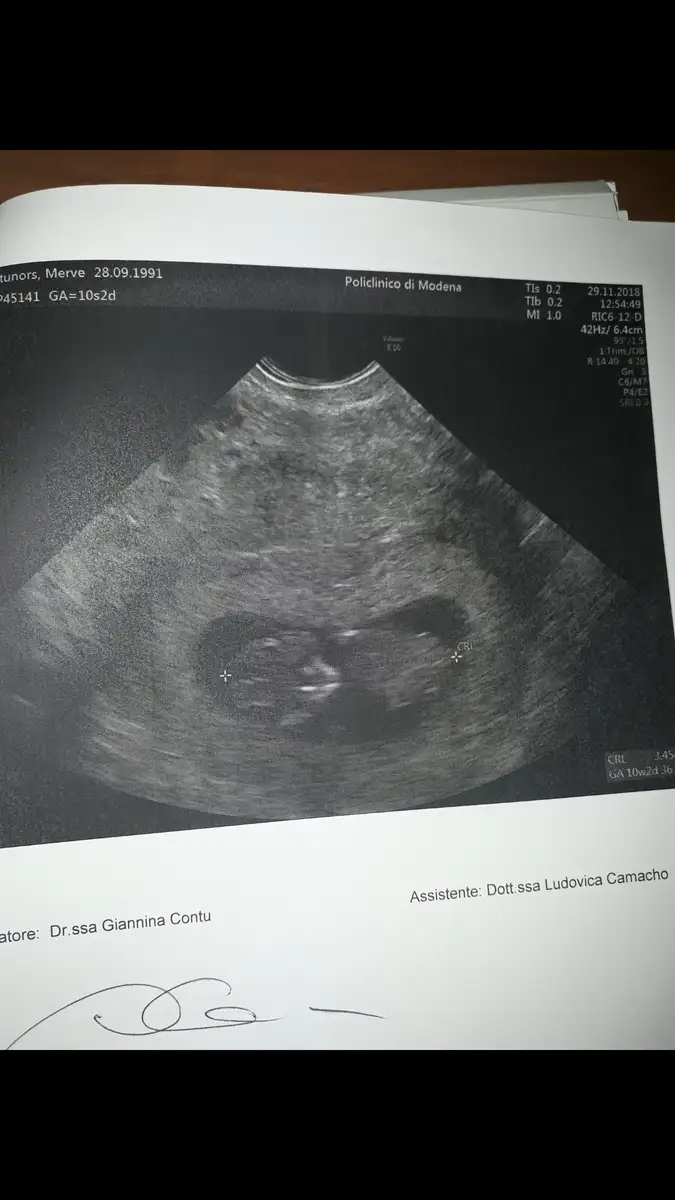

Gun icinde kac farkli pozisyonda duruyor bebekler endise etmeyin o an oyle yakalanmisKizlar bugün kontrolüm vardı annemlerin yanina 1 ayligina geldigim icin yurtdışında muane oldum burda 3.5 aylık olana kadar karindan bakmiolarmis kucuk belli olmuyor diye vajinal muane etti bebegin durusu dikkatimi cekti ters duruyor ilk kez böyle gördüm bebekler böylede ters dururmu ya

Kizlar bugün kontrolüm vardı annemlerin yanina 1 ayligina geldigim icin yurtdışında muane oldum burda 3.5 aylık olana kadar karindan bakmiolarmis kucuk belli olmuyor diye vajinal muane etti bebegin durusu dikkatimi cekti ters duruyor ilk kez böyle gördüm bebekler böylede ters dururmu ya

Bana da bakınsana kızlar nub ü gören var mı ultrasonda gördüm ben ama fotoda yok belki gören olur bi hayalet bir şey var köşede ama

Eki Görüntüle 2210521